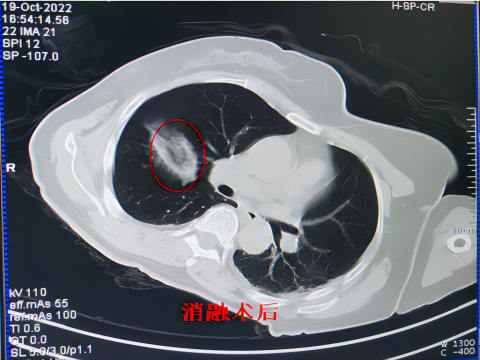

肿瘤在进行冷冻消融后,冷冻区域的“病灶”可能会显示扩大,这是正常的病理变化,只要术后按期随访观察,一般情况下,半年至一年内会吸收完全。